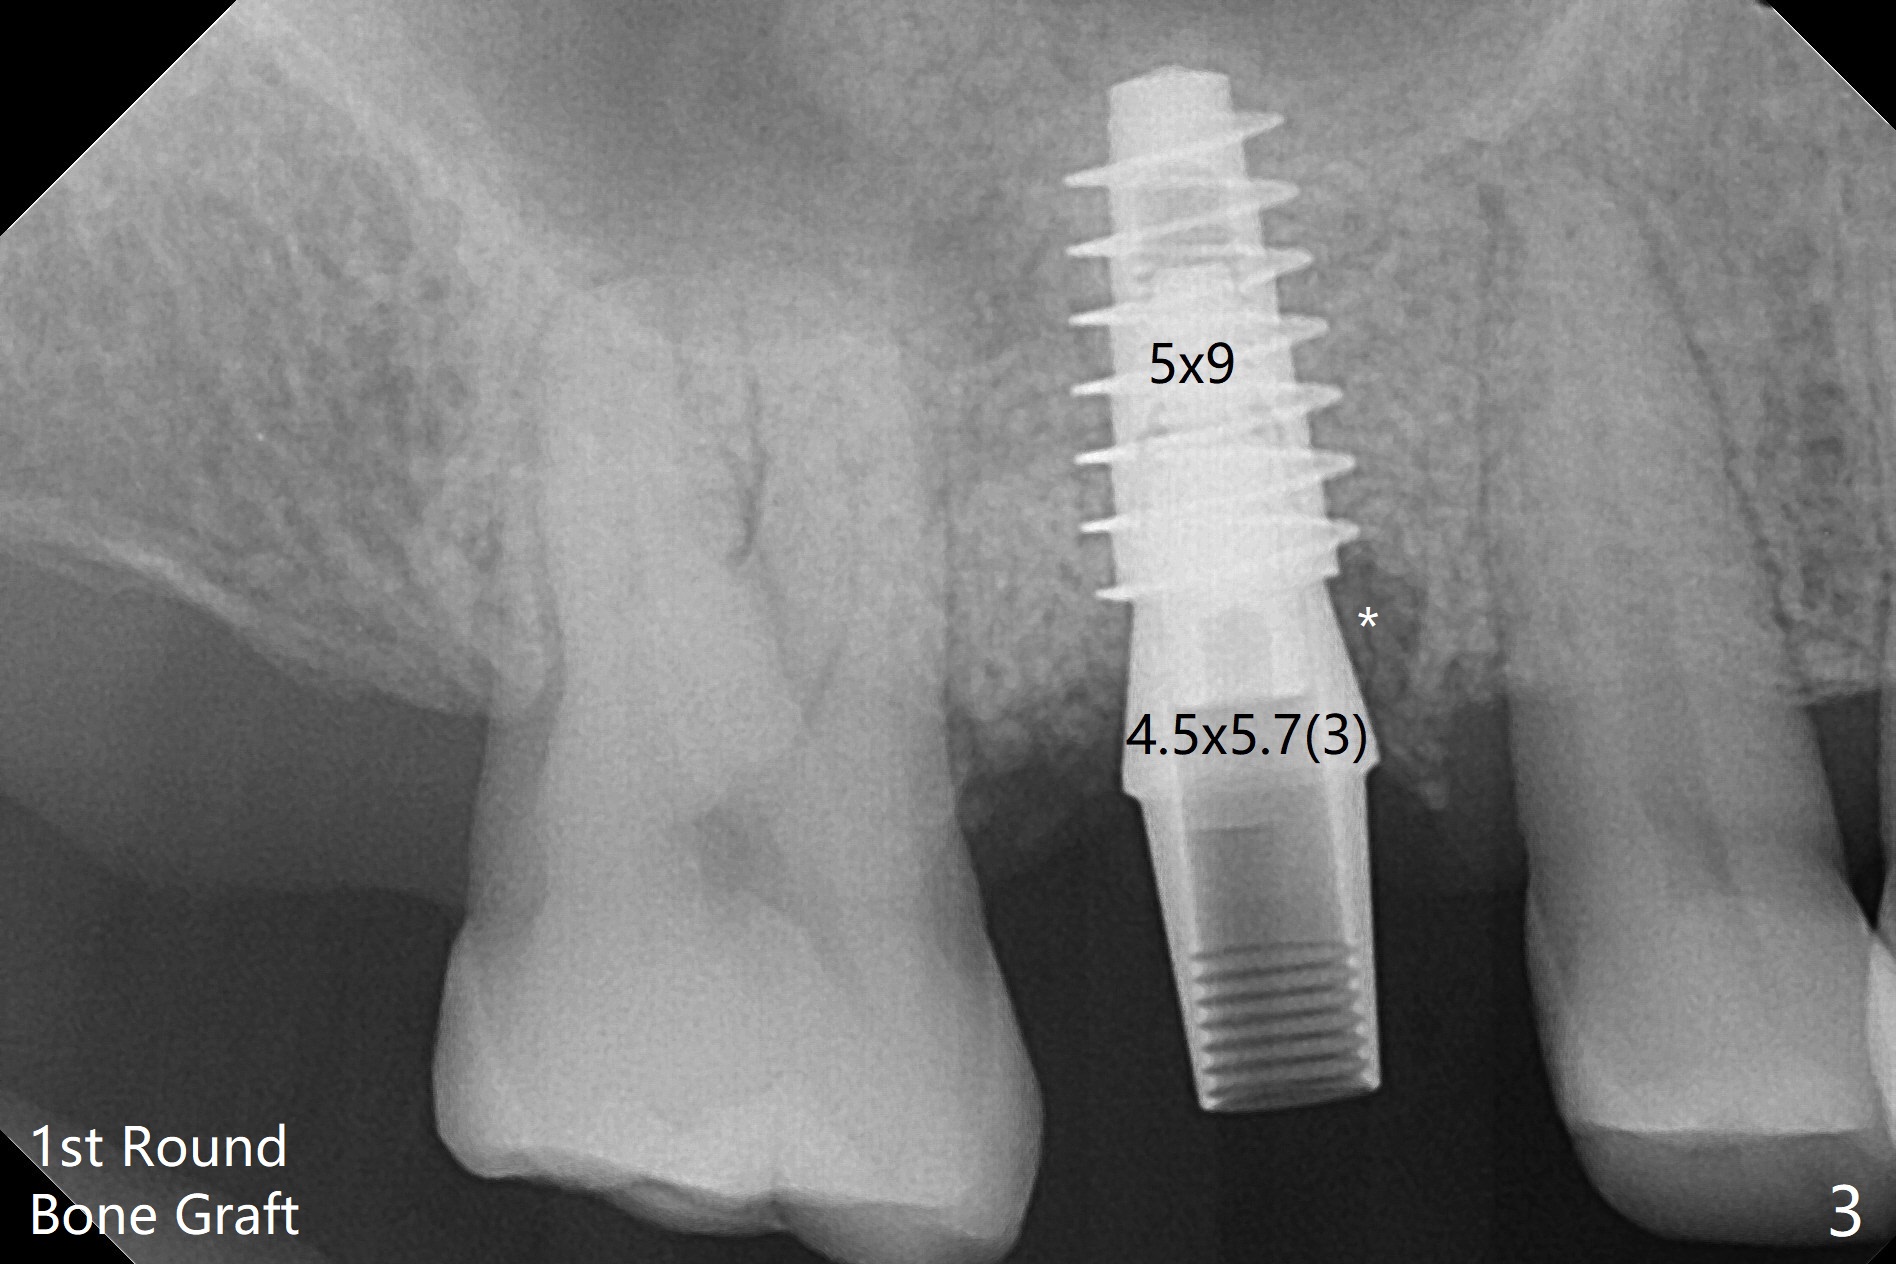

60岁男以前就害怕牙科治疗,一年前做一侧肾上腺切除,现在更紧张,不过挺配合。右上6手机切断拔除,虽然近中颊侧牙槽窝破坏厉害,中隔还很大(图一:S),利用导板顺利完成钻洞和提升术(图二:*)。植入正式植体后,放置第一轮粘性骨粉,至植体水平(确保植体深部周围没有缺失)而不影响基台置入,近中有不足之处(图三:*),第二轮骨粉补充(图四),最后覆盖PRF膜,临时牙冠固定。The crown/abutment/implant are found to have mild mobility 4.5 months postop, as related to #19 infection. A healing screw is placed. One month later, the wound heals; the bone density in the sinus increases (Fig.5 *), while that coronal to the implant decreases (^).愈合帽放置4个月,伤口还没有完全愈合,翻瓣后发现远中螺纹表面肉芽组织覆盖,去除后者,第一螺纹暴露。放置愈合基台后,从颊侧往远中缺陷填入骨粉(图六:*),缝合,覆盖树脂敷料。